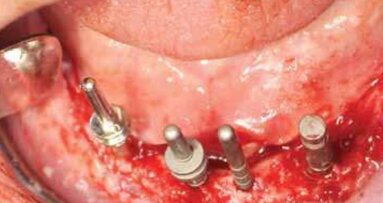

Kolejny etap, po 6-miesięcznym okresie gojenia obejmował procedury chirurgiczne polecające na ekstrakcji zębów 15 i 14, implantacji natychmiastowej w pozycji 15 oraz implantacji w pozycjach zębów 11, 21, 23, 24 wraz z augmentacją deficytów kostnych materiałem kościozastępczym i błoną zaporową (Ryc. 4). W celu rejestracji położenia płaszczyzny OA w stosunku do osi zawiasowej stawów skroniowo-żuchwowych użyto arbitralny łuk twarzowy. Do ustalenia relacji centralnej (RC) wykorzystano wewnątrzustną rejestrację zwarcia funkcjagrafem wg Kleinrok, który razem z łukiem twarzowym i artykulatorem stał się Technicznym Zespołem Modelowych (Majewski).

Po okresie gojenia tkanek miękkich przystąpiono do zabiegu pogrążenia 3 wszczepów śródkostnych w pozycji zębów 12, 21, 22 wraz z jednoczasową augmentacją deficytów kości xenograftem z resorbowalną błoną zaporową (Ryc. 14 i 15). Pomimo wystarczającej ilości miejsca, nie zdecydowano się na wprowadzenie 4 wszczepów śródkostnych